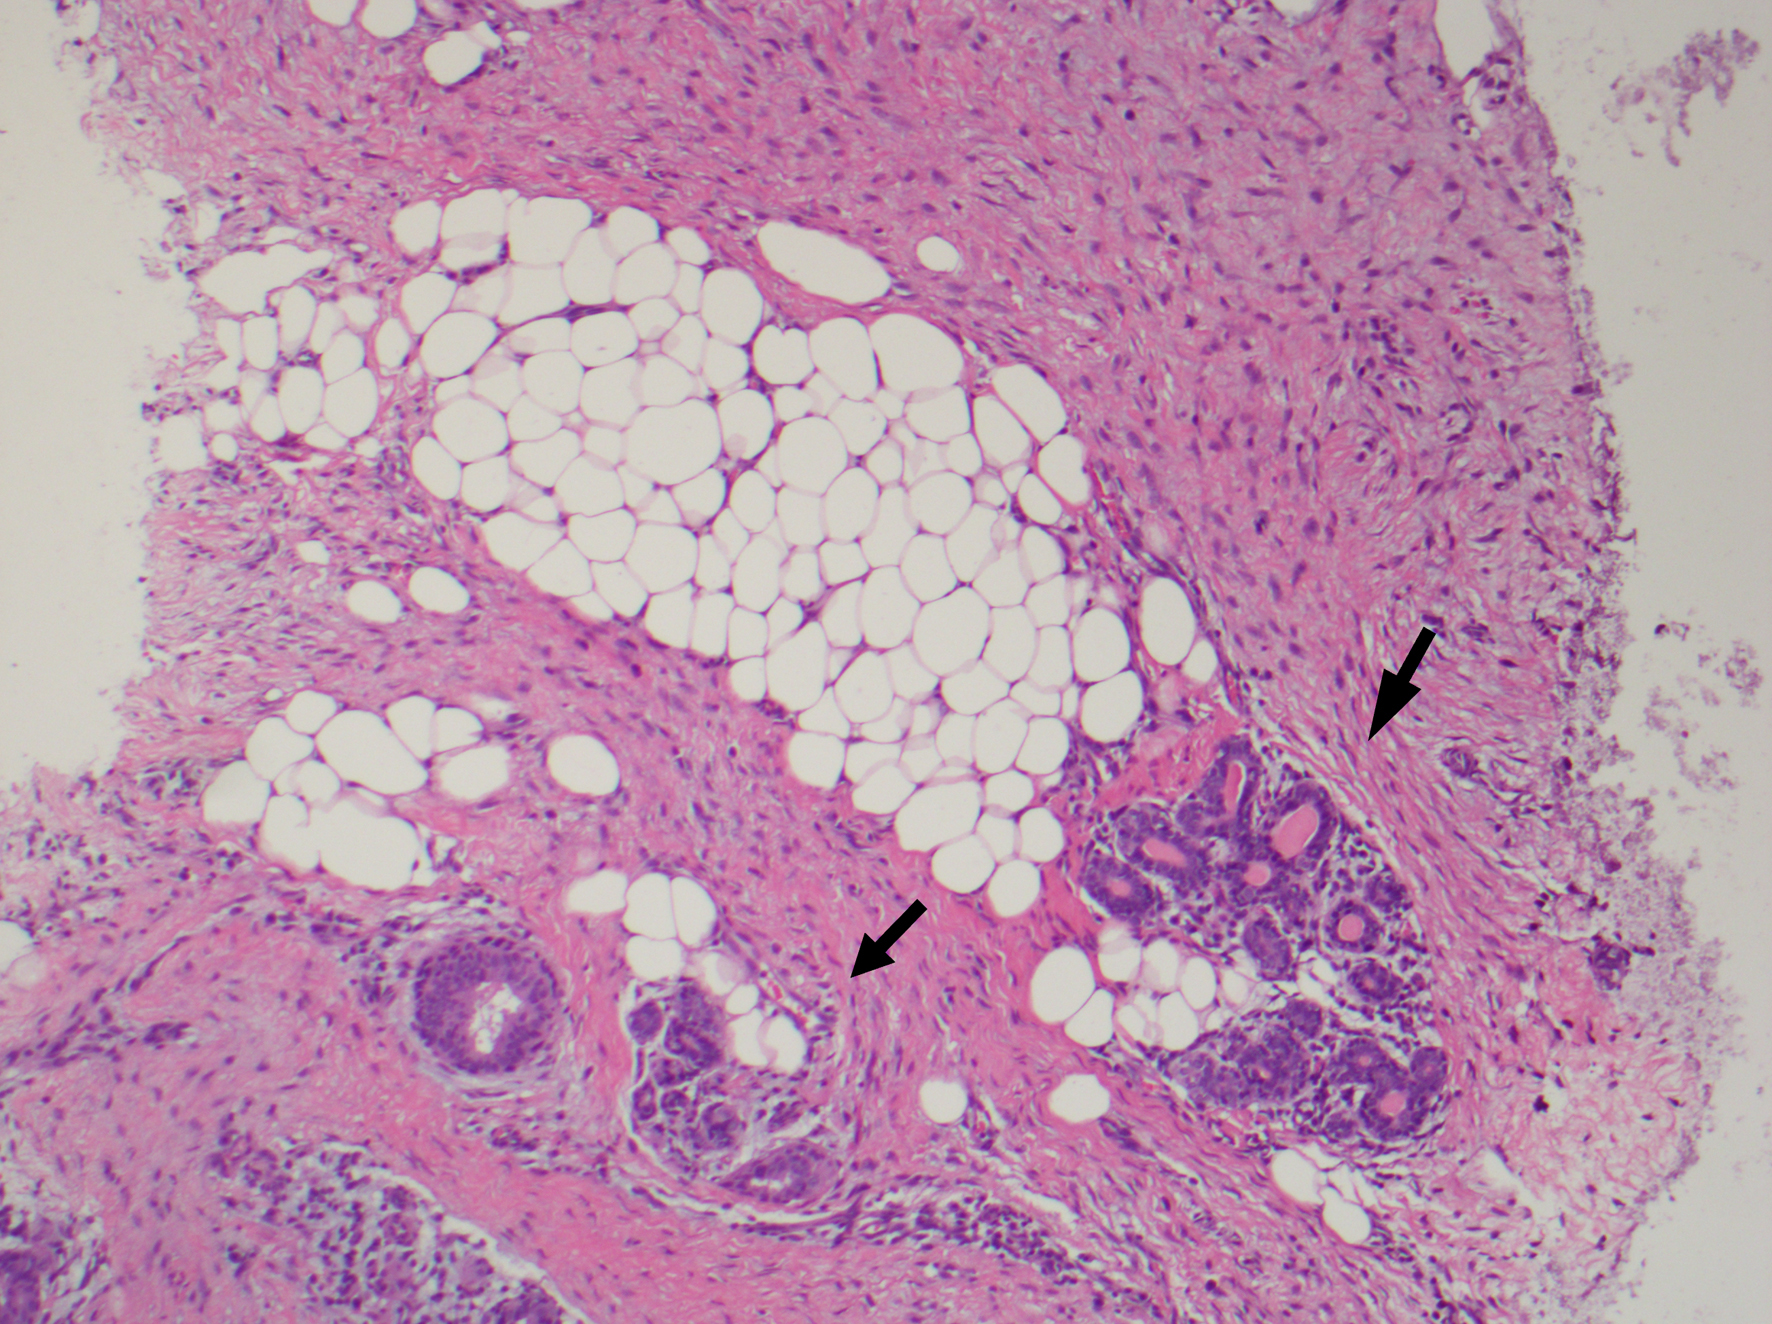

At pathology, Boland et al’s study noted bland spindle cell proliferation in all 15 specimens, most commonly seen with minimal nuclear pleomorphism, moderate cellularity, and collagen deposition. The cells infiltrate into or surrounding normal structures such as mammary terminal ductal lobular units or chest wall skeletal muscles with lymphocytic aggregates at the edges of the lesion (Fig. 1). On immunohistochemistry, six out of 15 were positive for actin, nine out of 15 were positive for beta-catenin, four out of 15 were positive for desmin, two were positive for S-100, and one was positive for CD34 [16]. Beta-catenin staining should be nuclear to consider it positive. Moreover, beta-catenin is not specific for fibromatosis and one should interpret the result with caution, as a good proportion of phyllodes tumor and metaplastic carcinomas express it (Fig. 2) [43].

![]() Click for large image | Figure 1. Fibromatosis infiltrating around normal breast epithelium (black arrow). |